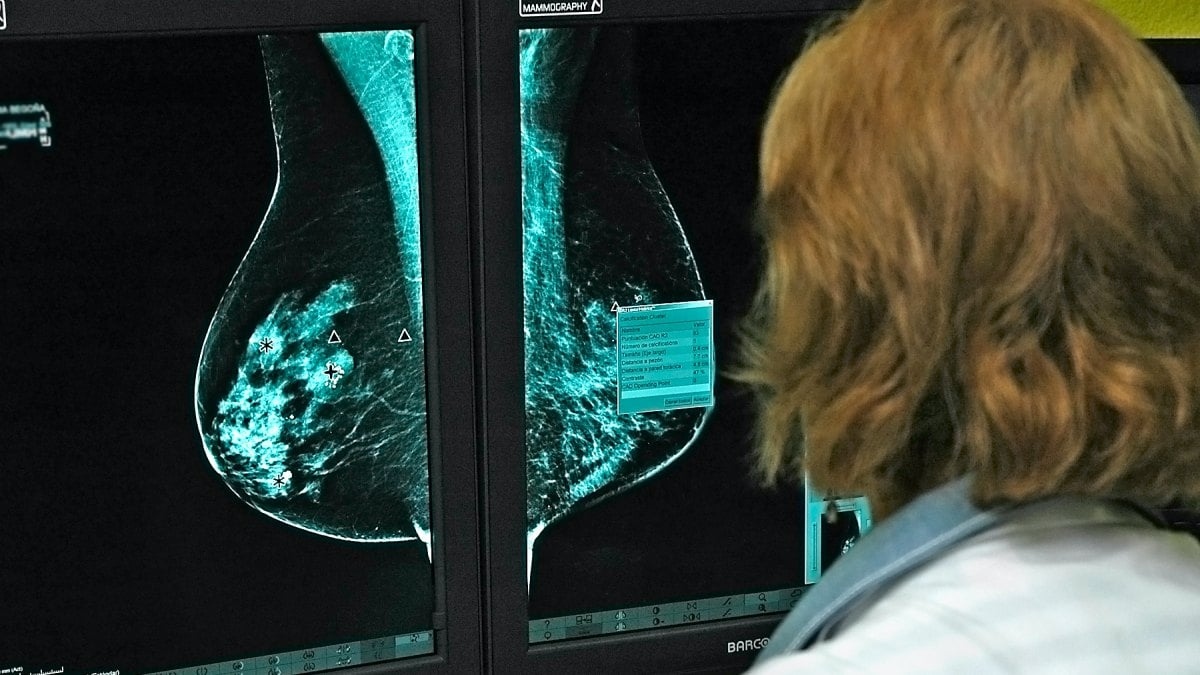

El cribado del cáncer de mama es una herramienta preventiva fundamental en la medicina moderna. Permite detectar tumores en fases tempranas, cuando el tratamiento es menos agresivo y las posibilidades de curación son significativamente mayores. En Castilla-La Mancha, se realizan más de 114.000 mamografías cada año a mujeres entre 45 y 70 años.

Sin embargo, cuando el sistema falla, como ha sucedido en Talavera, el tiempo se convierte en un enemigo temible. Un retraso de cinco meses en comunicar resultados y realizar pruebas pendientes puede significar perder una oportunidad crucial para detectar un tumor a tiempo. Lo más preocupante es que la incertidumbre y la falta de información alimentan el miedo y la desconfianza entre quienes esperan impacientes una llamada o un mensaje que les aclare su situación.